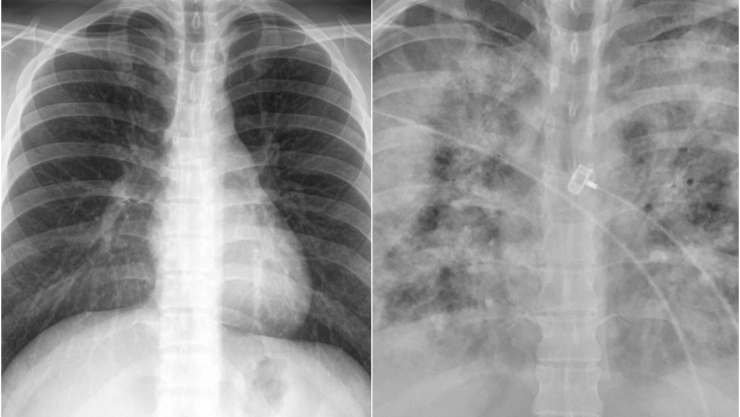

Faheem Younus, jefe del departamento de enfermedades infecciosas de la Universidad de Maryland, realizó una comparación con radiografías de pulmones de las personas no vacunadas contra las que sí se inyectaron contra el Covid-19.

En las imágenes que compartió en su cuenta de Twitter, Faheem Younus explicó que con la vacuna de Covid-19 se puede contraer la enfermedad, sin embargo, esta es generalmente leve, en comparación de las personas no vacunadas, que incluso llegan a la Unidad de Cuidados Intensivos (UCI).

Con la radiografía de los pulmones de personas no vacunadas y las que sí, el científico busca generar conciencia en la población para que se vacune, ya que puede ser la diferencia entre salvar la vida y no.

With Without

Vaccination Vaccination pic.twitter.com/GIcb5mJQz9